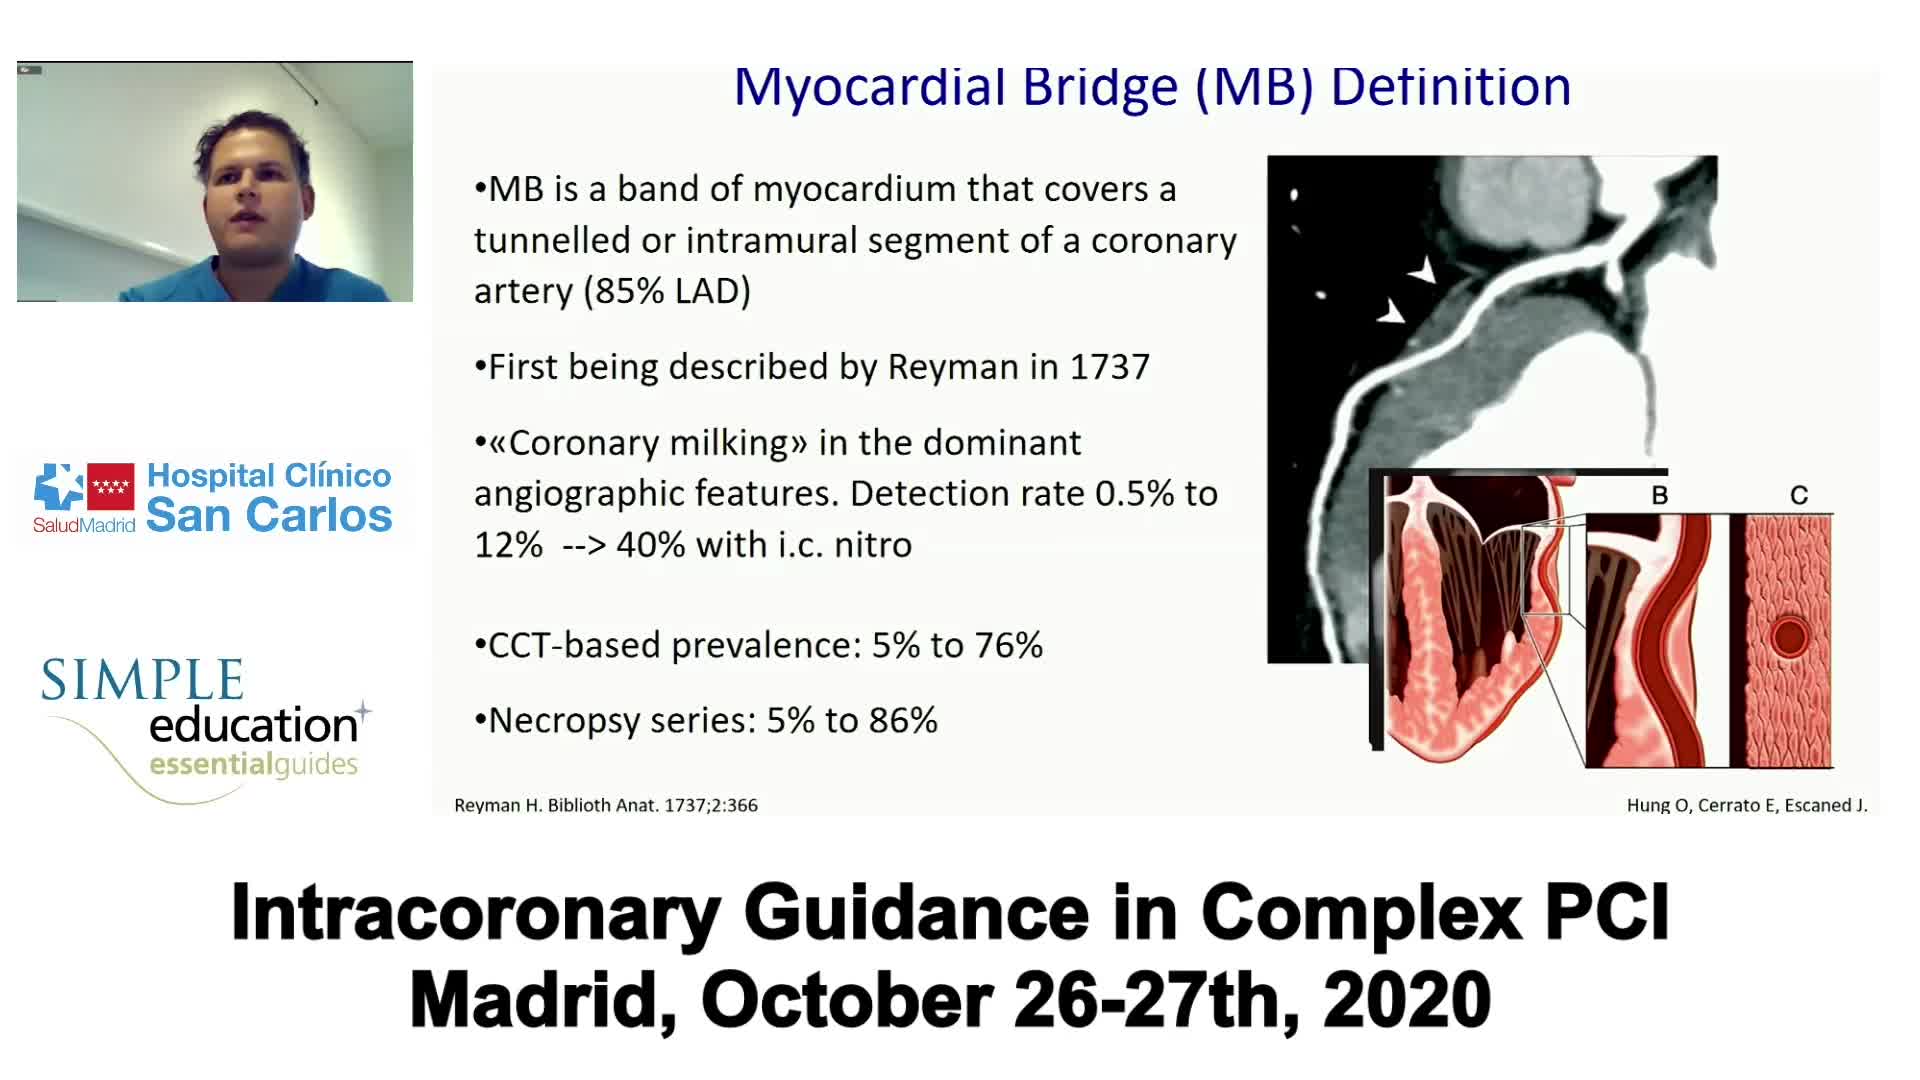

ABC for using Coronary Physiology in Aortic Stenosis, Primary Percutaneous Coronary Intervention (PPCI)/ACS, Muscle Bridges and Atrial Fibrillation - Dr Ricardo Petraco

Best practices and personalised medicine in complex PCI - Prof Javier Escaned

Intracoronary guidance in acute coronary syndromes - Dr Hernan Mejia-Renteria